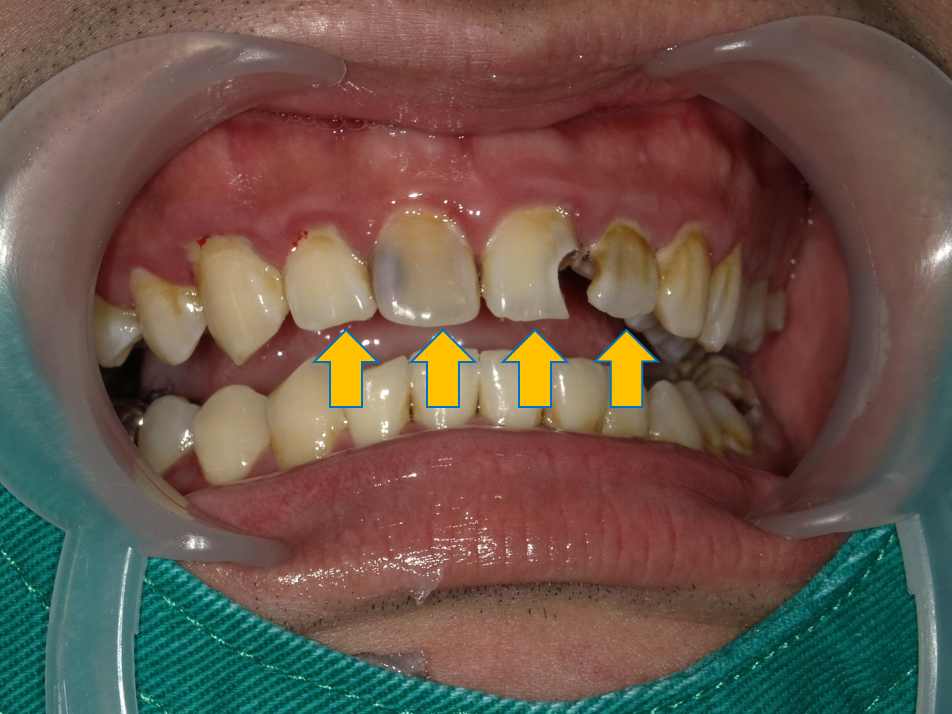

案例 1 術前(Before)

門牙部分缺損磨耗,造成咬合問題